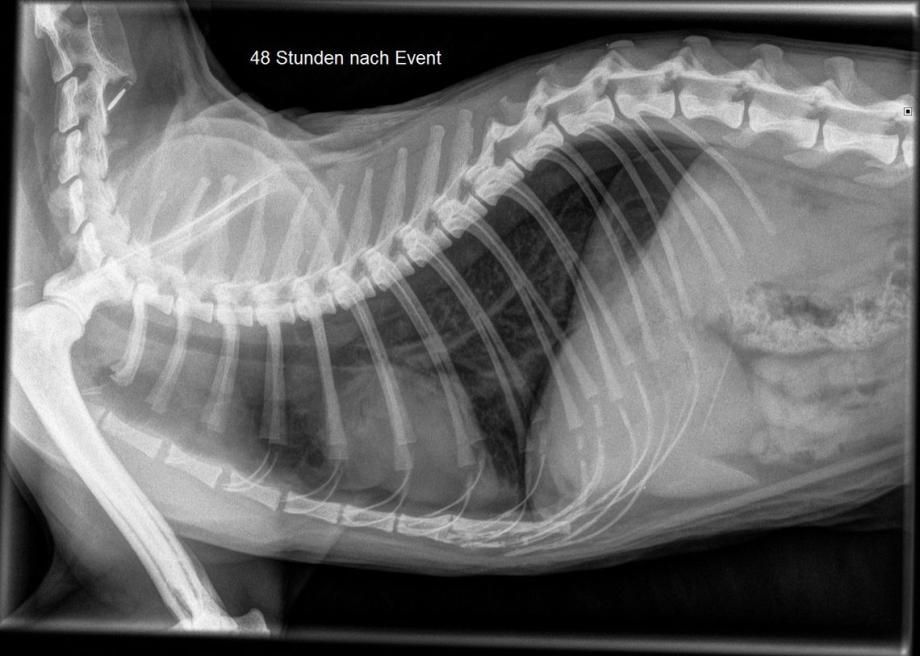

Muffin geht es beständig besser; 2 Tage nach Entstehen des Problemes wird erneut ein Bruströntgen angefertigt - der Pneumothorax ist praktisch verschwunden und in der Lunge hat sich die Flüssigkeitsansammlung praktisch komplett abgebaut. Der Kater wird deshalb wieder nach Hause entlassen.